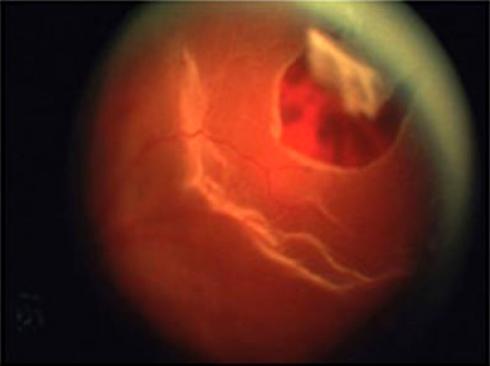

Desgarros Retinianos

La parte posterior del ojo contiene un gel llamado ví­treo. El cuerpo ví­treo esta casi en su totalidad con la retina. El gel ví­treo experiment...